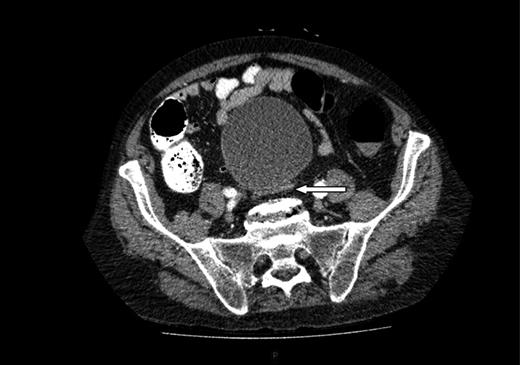

A computed tomography (CT) of the abdomen and pelvis was performed. This showed a grossly distended urinary bladder and compression of the sigmoid colon against the sacral promontory causing bowel obstruction (Figs 1 and 2, respectively) as well as a 4.9 cm abdominal aortic aneurysm without any signs of a rupture (Fig. 3). The plan was to consult our vascular colleagues regarding management of the AAA once the obstruction had settled.

Abdominal aortic aneurysm with some wall standing thrombus but without any signs of rupture.

Following a CT scan of the abdomen and pelvis, he was found to have a distended bladder causing large bowel obstruction by pressing the bowel against the sacral promontory and what appeared to be an incidental 4.9 cm AAA without any signs of rupture (Figs 1–3).